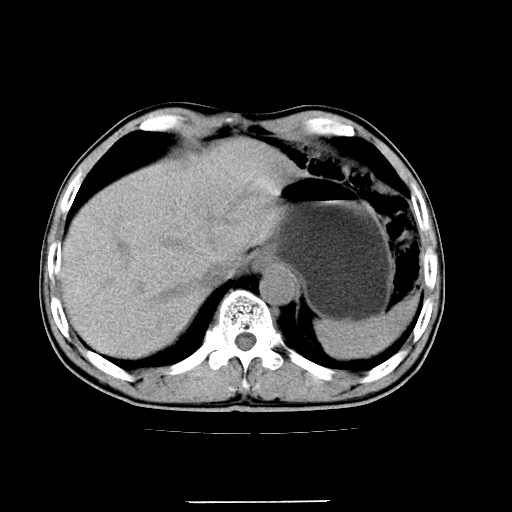

应该考虑是肠管,理由1、平扫和增强对比,形态和内部的密度有明显改变。2、增强图片可见明显气液平面。

是肠管影,肠壁有强化。

一个形态变化大应该是肠管。

另一个上下观察不成形,强化也不符合淋巴结表现故考虑术后改变。

另外,胰腺体部密度在平扫和增强时均不太均匀,似有数个小的囊状低密度区存在。不知道增强时其他期如何?应该高度警惕为转移性病变。

胰头右侧低密度影卡考虑为肠管;胰头前部低密度影,增强环形强化,结合临床首先考虑转移灶,其次考虑淋巴结结核(中心干酪性坏死)。